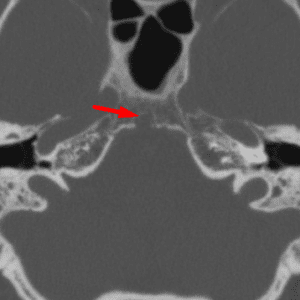

Arachnoid Granulation

Mimicking thrombus